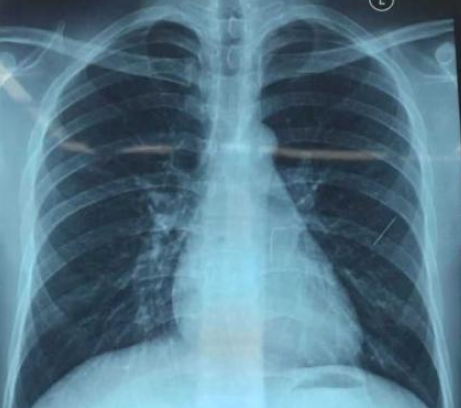

第二天一大早,她打车来到了吉林省肿瘤医院,原来是要给我拍一个帅气的照片,这可给我高兴坏了,先来一个我的全身照。

来来来,再来个局部特写,等等……什么情况?CT报告单提示右肺部小结节,建议MDT会诊?

网上/APP上预约诊疗、现场自助机取号、自助缴费,整个过程非常顺畅,一气呵成,终于轮到我的主人看病了,来一个现场的照片。影像科专家说需要做一个小结节分析,于是又给了我一个特写。